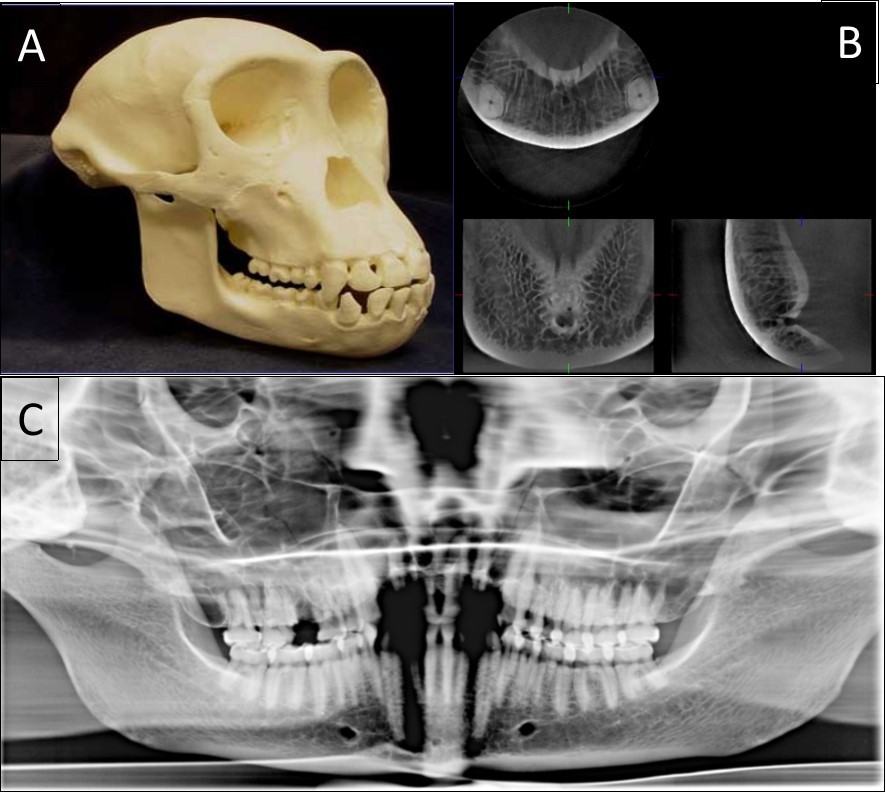

The typical images from modern human and great apes with different anatomical features were shown in Figure 1 and Figure 2. A group of variables were categorized as: the presence of the incisive canal, the number of mandibular canal bifurcations, the potential occurrence of an anterior loop, the presence of the incisive canals, its end-point and connection of the incisive to the lingual canals (Figure 3). Interspecific variability was determined by comparing contemporary human and great ape mandibles. In this analysis, mandibles from the different geographical locations were grouped in the human group, and then compared to mandibles of chimpanzees and gorillas.

Figure 1.The classical sample images with different anatomical features. A general view of a 20-year-old chimpanzee (A), its three-dimensional CBCT view (B) and two-dimensional panoramic view (C).

The classical sample images with different anatomical features. A general view of a 20-year-old chimpanzee (A), its three-dimensional CBCT view (B) and two-dimensional panoramic view (C).